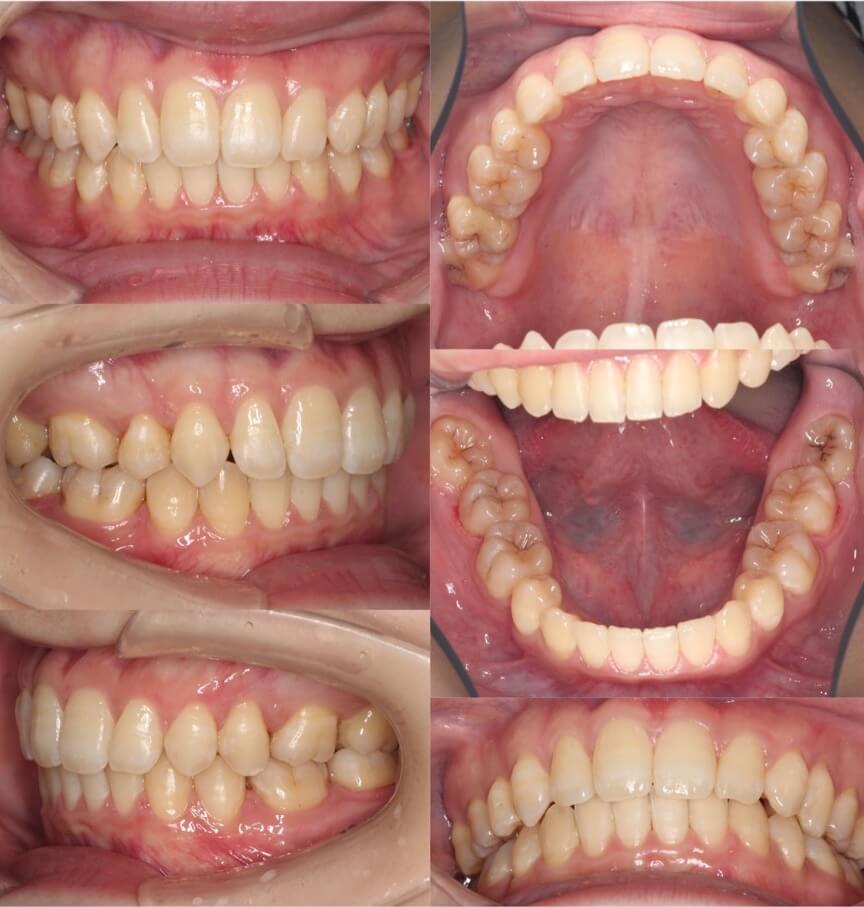

30代女性・先天性欠損4歯・5番欠損

<症例概要>

主訴:口元の突出・乳歯の残存

年齢・性別:30代女性

症状:上下第二小臼歯先天性欠如・乳歯晩期残存・上下顎前突

治療方針:抜歯空隙閉鎖

治療装置:唇側矯正装置

固定源:下顎圧下アーチ

抜歯:上下乳臼歯(計4本)

治療期間:2年10か月

リテーナー:上下プレートタイプ+下フィックスタイプ

治療費用:964,000(税込)

代表的副作用:痛み・治療後の後戻り・歯根吸収・歯髄壊死・歯肉退縮

上下とも前から数えて5番目の歯が先天的欠損しているケースです。もともと口元が前方に突出している傾向にあったため、残存している乳歯を抜歯して前歯を後方に引っ込める治療を行いました。

乳臼歯は本来あるべき永久歯よりサイズが大きい傾向にあり、抜歯後の空隙閉鎖には通常より時間がかかります。下のワイヤーを2重にして少し強めの力をかけて治療期間の短縮を計画したのですが3年弱かかりました。

奥歯の先欠歯の抜歯矯正治療は、一般的な小臼歯抜歯矯正と比較して治療期間がかかる傾向になります。